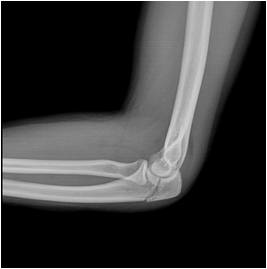

The elbow is made up from 3 bones; the humerus, the radius and the ulna. It is what we call a “hinge joint”. The joint is held strong by a capsule, ligaments and muscles.